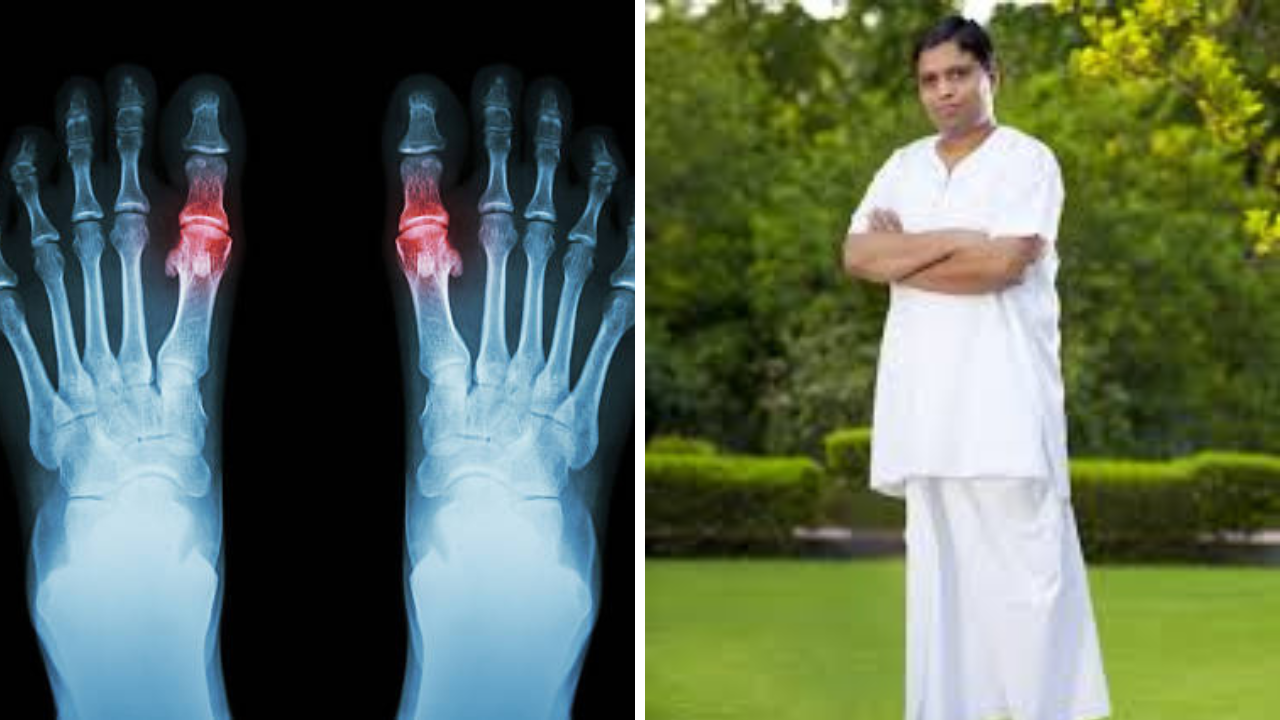

• Acharya Balkrishna यांनी सांगितला Uric Acid चा उत्तम उपाय, ‘चमत्कारी औषधा’ने होईल विषाचा खात्मा

Acharya Balkrishna यांनी सांगितला Uric Acid चा उत्तम उपाय, ‘चमत्कारी औषधा’ने होईल विषाचा खात्मा

शरीरात युरिक अ‍ॅसिड वाढल्यास आचार्य बाळकृष्ण एक खास पावडर खाण्याची शिफारस करतात. ही पावडर कशी बनवायची आणि ती तुमच्यासाठी कशी फायदेशीर ठरू शकते तेदेखील जाणून घ्या